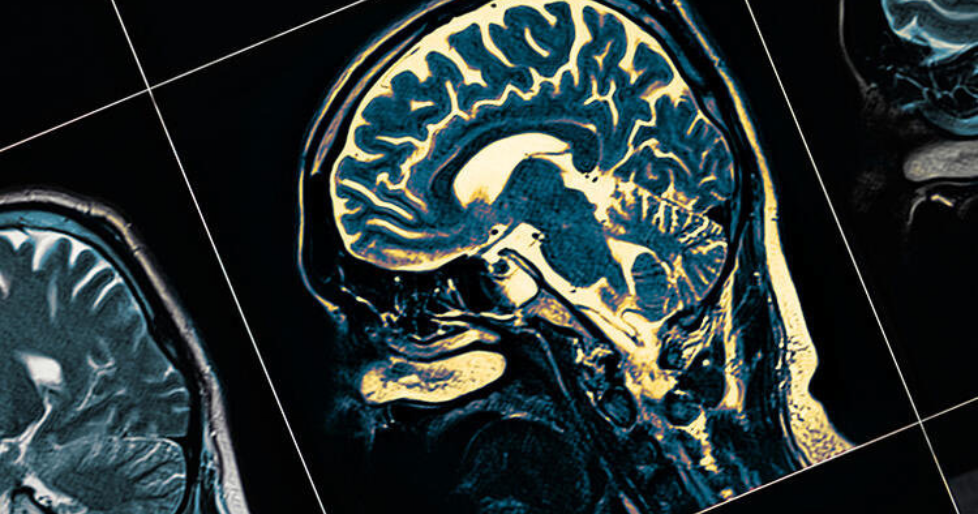

Beyinde enfeksiyona yol açan ve genellikle ölümcül olabilen, mikro ölçekli ve tek hücreli Naegleria fowleri burun yoluyla insan vücuduna giriyor.